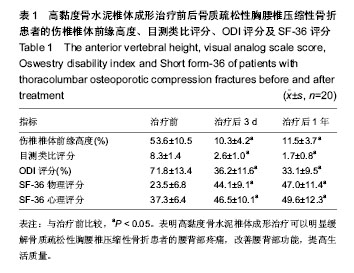

2.1 参与者数量分析 20例患者均顺利完成手术,完成1年以上随访,按意向性处理分析,20例均进入结果分析。 2.2 伤椎椎体前缘高度恢复 治疗后患者伤椎椎体前缘高度得到明显改善,由治疗前的(53.6±10.5)%到治疗后 3 d的(10.3±4.2)%和治疗后1年的(11.5±3.7)%,治疗前后椎体高度比较差异有显著性意义(P < 0.05),治疗后3 d和治疗后1年椎体高度比较差异无显著性意义(P > 0.05),见表1。 2.3 腰背部疼痛及功能恢复情况 术后腰背部疼痛明显缓解或消失,腰背部功能明显改善,生活质量评分得到明显提高,治疗后3 d及1年的目测类比评分、ODI评分明显低于治疗前(P < 0.05),治疗后3 d和治疗后1年的目测类比评分、ODI评分比较差异无显著性意义(P > 0.05)。治疗后3 d及1年的SF-36物理评分及心理评分均高于术前(P < 0.05),治疗后3 d和治疗后1年的SF-36物理评分及心理评分比较差异无显著性意义(P > 0.05),见表1。治疗后神经功能均正常为Frankle E级,与治疗前相同。 2.4 并发症及不良反应 所有手术均顺利完成,每个椎体注射骨水泥量2-5 mL,术中血压及血氧饱和度均正常。治疗后随访12-18个月,平均14.5个月。术后复查X射线及CT见骨水泥弥散良好,只有1例发生椎管内少量骨水泥渗漏及1例椎体前方渗漏,但无任何临床症状,无骨水泥毒性或过敏反应、肺栓塞、感染和神经损伤等并发症发生。随访期间无新发骨折。"